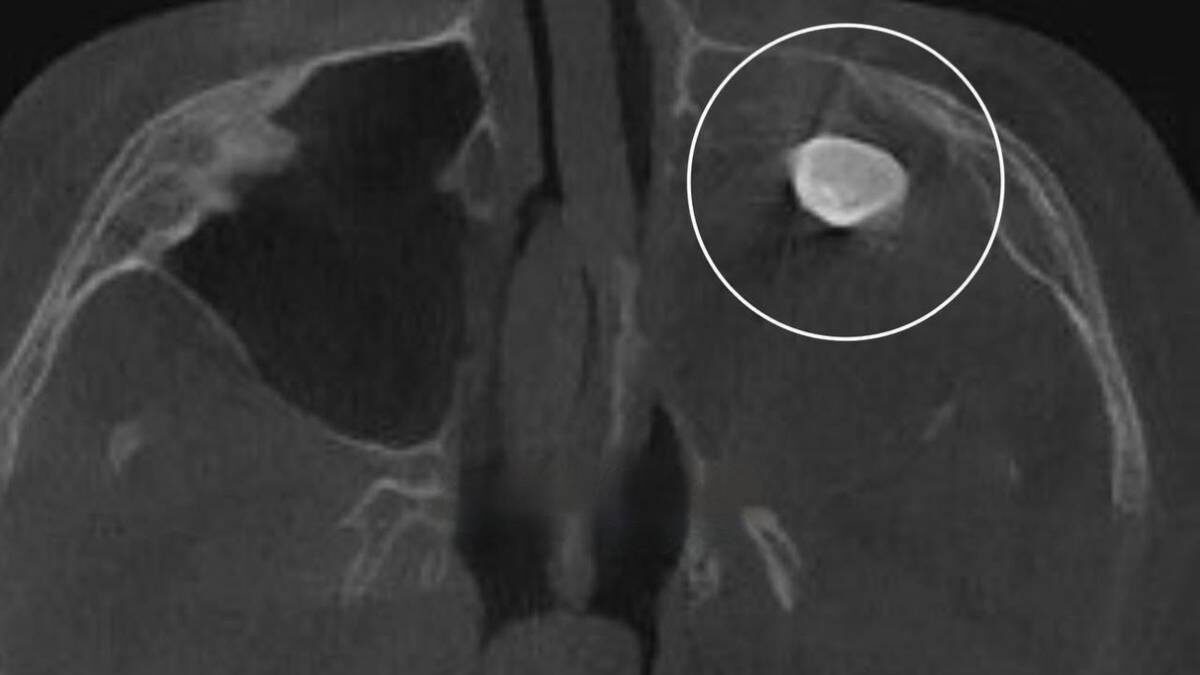

Опухоль с зубами, волосами и костями: что такое тератома и насколько она опасна

15-летний подросток из Москвы обратился к врачам с жалобами на заложенность носа и асимметрию лица. При обследовании у него в гайморовой пазухе обнаружили зуб, ребенку поставили диагноз — тератома. Насколько эта болезнь опасна и по каким признакам ее можно распознать, выясняла «Вечерняя Москва».